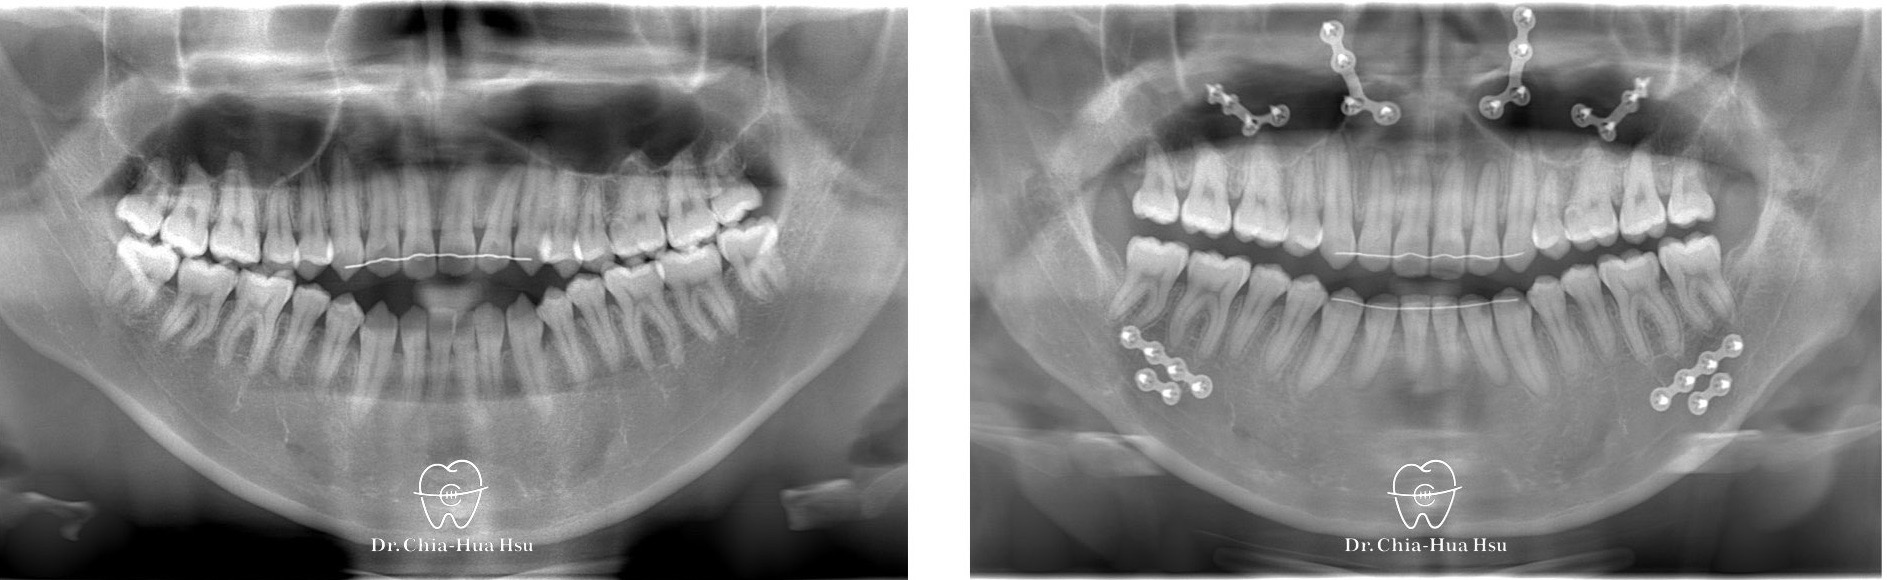

戽斗、開咬、齒列不正

• 病患主訴:戽斗、前牙開咬。

• 問題分析:患者是標準的骨骼三類咬合(Skeletal Class III),下巴明顯較長,還有上顎牙弓過窄、開咬以及齒列不正。

• 治療方式:使用傳統金屬矯正器,合併正顎手術(雙顎),上顎拔除兩顆小臼齒以利手術方式進行上顎牙弓擴寬。

• 治療時間:1 年 7 個月。

• 治療結果:齒列排齊,咬合功能恢復,外觀更和諧。

治療前

治療後